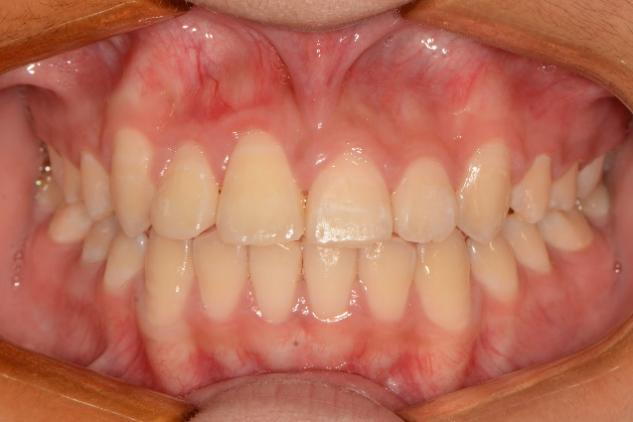

Now the lucky girl can happily show her bright and confident smile with no embarrassment any longer. With publication of this featured case report, the innovative orthodontic techniques, particularly the self-developed high-efficiency torquing auxiliary “gate spring”, will be applied by more orthodontists around the world to benefit their patients.